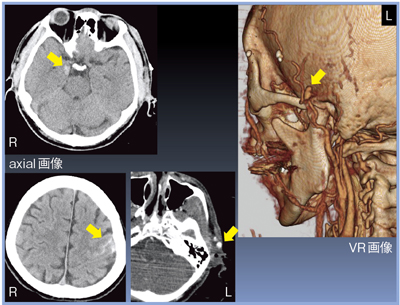

1mm厚の再構成画像では,axial画像で右側頭葉の脳挫傷,左頭頂葉のクモ膜下出血,VR画像で左浅側頭動脈の損傷を認めた(図1)。

![]() 図1 症例1:1mmスライス厚の再構成画像 ←左浅側頭動脈の損傷 |